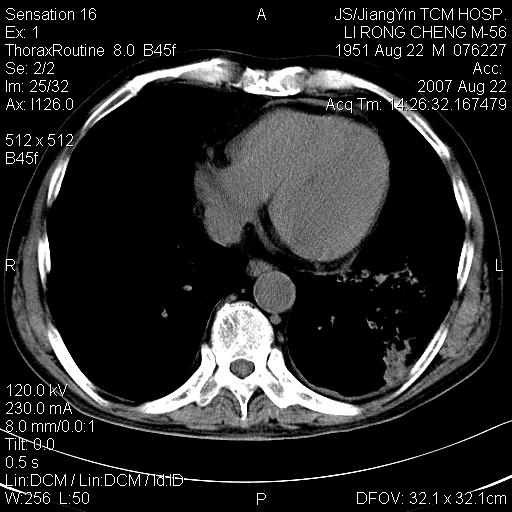

标题: CT9479:M,56Y,DM病史,咳嗽发热5天.肺脓疡.肺癌? [打印本页]

标题: CT9479:M,56Y,DM病史,咳嗽发热5天.肺脓疡.肺癌?

边灶边缘较光整,冠状位病灶呈大片状,,内有空洞,有胸膜反应,但无明显胸膜外侵犯征像,结合病史支持考虑肺肿脓,不排除结核,治疗后复查

好多钙化灶哦,病灶位于下叶背段,或许考虑结核更合适,做下相应检查先

左肺下叶见类软组织密度影,其内密度不均,有小空洞,广基与胸膜相连,其周见斑片状致密影.

考虑肺肿脓,不排除结核.

左肺下叶支气管呈小囊状扩张。下叶背段有类圆形高密度影,边缘模糊,外与胸膜相连。左侧胸膜增厚粘连。心包膜增厚。结合病史考虑1支扩并感染2胸膜及心包炎。

左下肺团片状类软组织密度影,形态不规则,边缘欠规整,其内可见液化区及气体影,病灶内侧见引流支气管影,相邻胸膜反应性增厚。病灶周围肺野内见增粗支气管,壁厚,边缘模糊。考虑:支气管扩张并感染;肺脓肿。